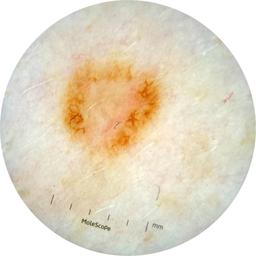

ISIC_3176953

Information

2135 x 2135

Clinical

Field Value

acquisition_day 410

age_approx 40

anatom_site_1 Head and neck

anatom_site_general head/neck

concomitant_biopsy False

diagnosis_1 Malignant

diagnosis_2 Malignant adnexal epithelial proliferations - Follicular

diagnosis_3 Basal cell carcinoma

diagnosis_confirm_type single image expert consensus

family_hx_mm False

fitzpatrick_skin_type I

image_manipulation instrument only

image_type dermoscopic

lesion_id IL_4059380

patient_id IP_8700330

personal_hx_mm True

sex female